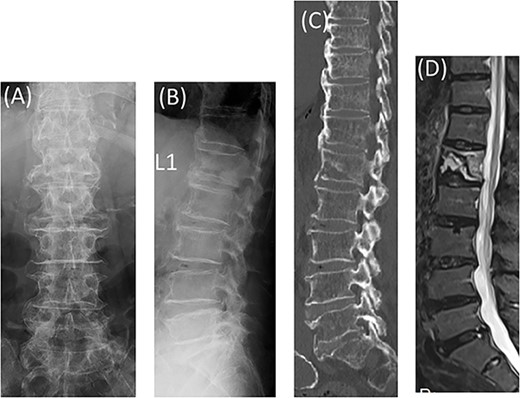

The patient complained of lower back pain during motion; however, no neurological deficit was noted. Radiographs of the thoracolumbar spine showed L1 vertebral body deformation (Fig. 1A and B). Computed tomography (CT) revealed anterior bony bridging by DISH from T1 to L1 and a vertebral fracture with bony defects in the caudal part of the L1 vertebral body (Fig. 1C).

Radiographs showed L1 vertebral body deformation (A, B). CT and MRI STIR revealed anterior bony bridging by DISH and a vertebral fracture in the caudal part of the L1 vertebral body (C, D).

Magnetic resonance imaging (MRI) showed hyperintensities on short inversion time (TI) inversion recovery (STIR) in the L1 vertebral body, indicating a single caudal endplate fracture and ligament failure of the posterior element (Fig. 1D).

The diagnosis was an L1 vertebral fracture at the caudal end of DISH.